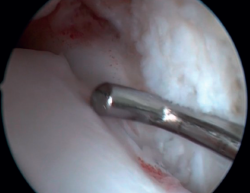

El ligamento de Bassett debe conservarse siempre que no tenga un aspecto patológico, descartando engrosamientos, roturas parciales o lesiones recíprocas en la superficie anterolateral del astrágalo (Figura 6), que se asocian a inestabilidades anterolaterales o rotatorias. La inserción peroneal se usa como referencia para localizar la inserción distal del LTFA. Debe inspeccionarse el ligamento deltoideo en la gotera medial en caso de sospecha de inestabilidad rotatoria asociada. Durante la artroscopia, se puede realizar una reparación directa de los ligamentos mediante suturas y anclajes.

Figura 6. Surco producido por el roce de la cúpula talar con el ligamento de Bassett, visible tras la resección de este. El ligamento presentaba una rotura parcial y un engrosamiento cicatricial.

La resección de osteofitos se realiza deslizándose desde su parte superior, rebajando gradualmente hasta alcanzar la zona articular (Figura 2). Con una pinza de tipo basket se puede resecar la zona más cercana a la articulación (Figura 5). Suele ser útil intercambiar los portales de visión y trabajo para visualizar y resecar completamente los osteofitos. Para el pinzamiento de partes blandas, un sinoviotomo de 3,8 o 4 mm suele ser suficiente. El vaporizador es útil en pinzamientos compactos, típicos de condiciones postraumáticas o reintervenciones, también para delimitar la parte ósea del osteofito antes de su resección.